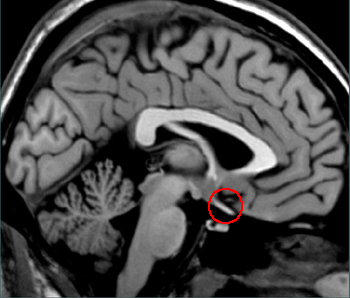

Is this fiber bundle the optic tract or nerve?

(Click on the correct response)